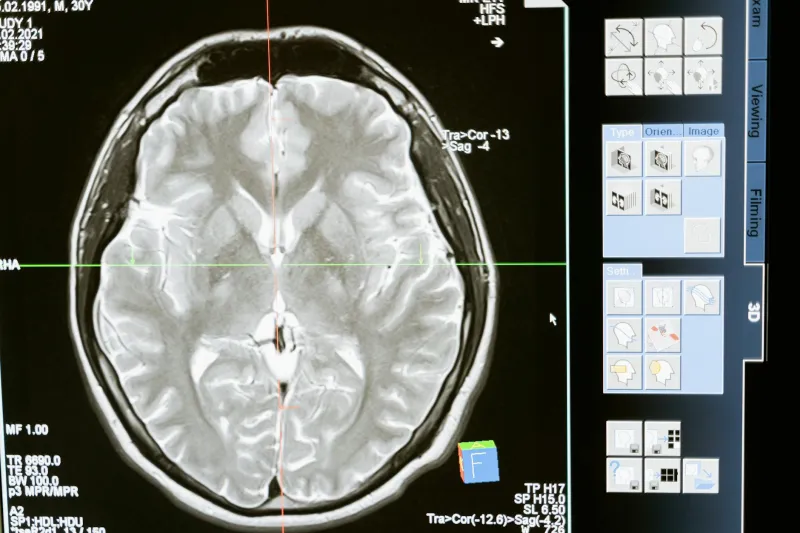

Today's neuroscience technology — including fMRI and PET scans — allows researchers to observe healthy brains in action. What they've consistently found contradicts the left-brain, right-brain personality model.

A comprehensive 2013 study from the University of Utah analyzed brain scans from over 1,000 people aged 7 to 29. Researchers measured activity across 7,000 brain regions while participants performed various tasks. Their conclusion? While certain brain functions do show lateralization, there's no evidence that individuals preferentially use one hemisphere over the other.

"It's absolutely true that some brain functions occur in one or the other side of the brain," explained lead researcher Jeff Anderson. "Language tends to be on the left, attention more on the right. But people don't tend to have a stronger left- or right-sided brain network."

Virtually every cognitive task — whether it's solving a math problem, creating art, or processing emotions — engages networks that span both hemispheres. Your brain operates as an integrated whole, not as two competing personalities.